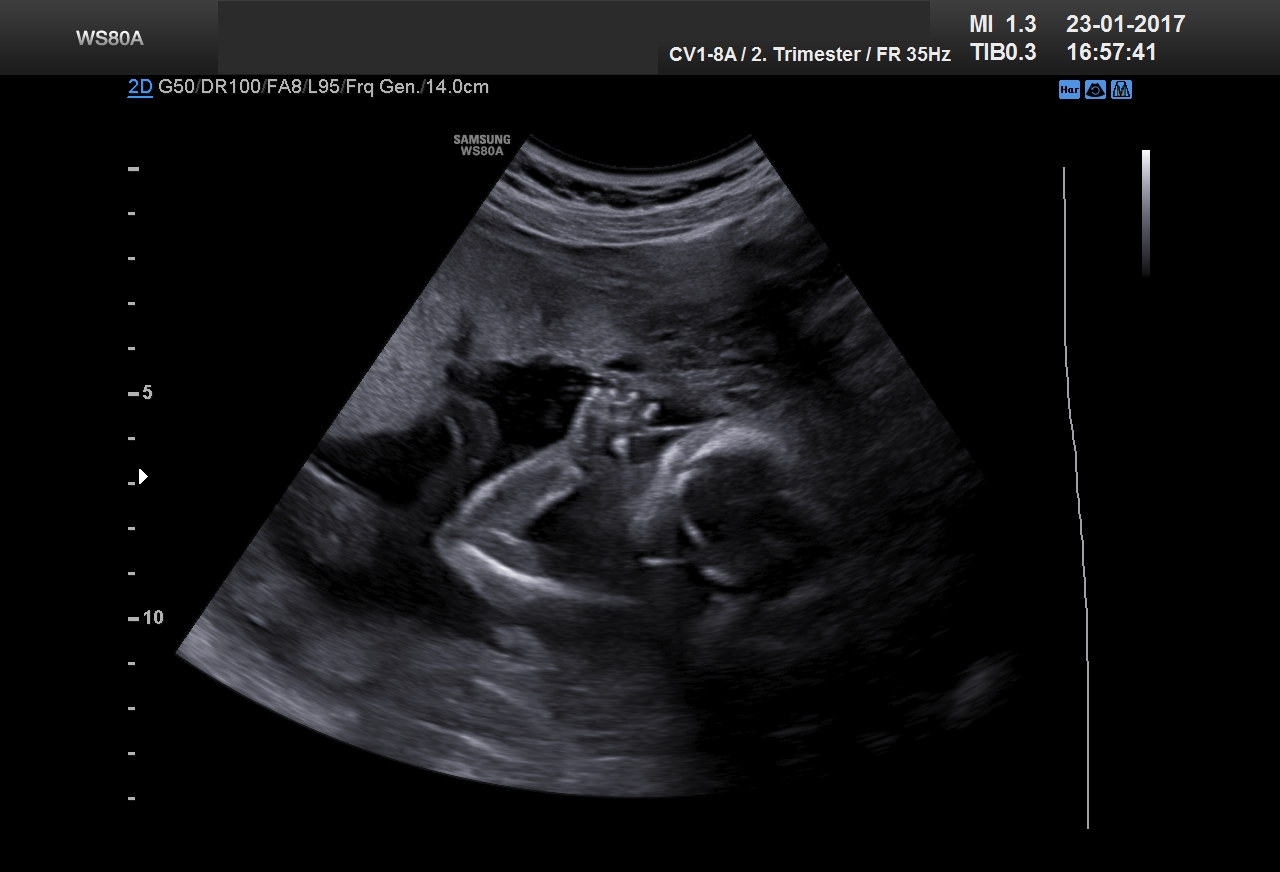

21. Woche